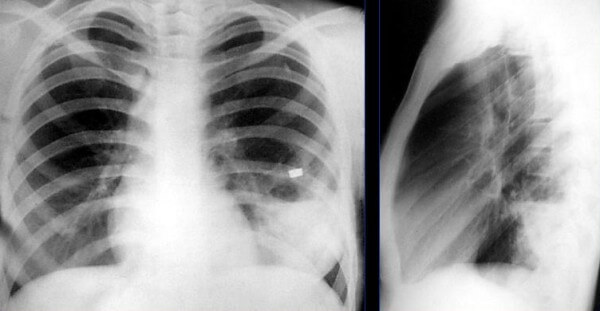

На снимке видны отдельные небольшие очаги поражения ( 1-1,5 см), расположенные в одном из легких (при билатеральной форме – в обоих). Заметным в данном случае будет расширение корней легких из-за наполнения жидким экссудатом.

Снимок при очаговой пневмонии

Сегментарная пневмония – воспаляется целый сегмент легкого. Данная форма пневмонии может осложниться ателектазом (спадением части легкого с полной потерей его воздушности. Сегментарная форма воспаления может быть проявлением длительной затяжной пневмонии, переходящей в легочный фиброз или осложненной локальным хроническим бронхитом. На рентген-снимках виден целый сегмент, пораженный воспалением.

Снимок при сегментарной пневмонии

- Очаговая форма. На рентгене отображаются небольшие (1-1,5 см) тени со слабой или умеренной интенсивностью окраски, неоднородной структурой и нечеткими границами. Очаги поражения могут быть единичными или множественными, а в некоторых случаях они сливаются в одно большое пятно. Корни легких расширены, причем нарушения нормального рисунка органа могут сохраняться в течение нескольких дней после выздоровления.